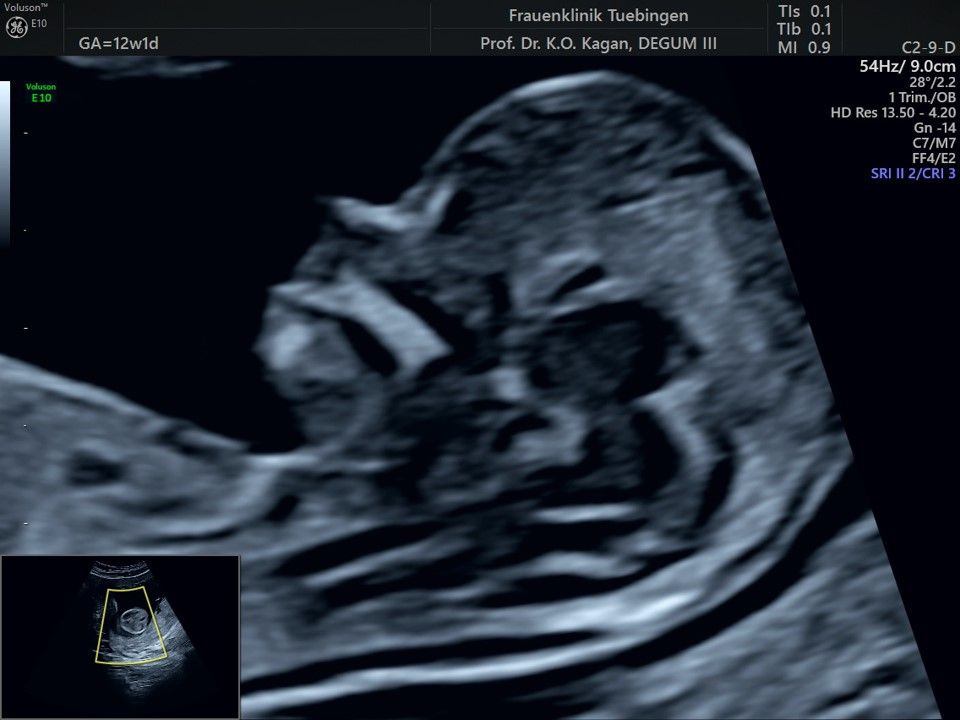

Im Rahmen des Ersttrimester-Screenings untersuchen wir die Organe des Feten mittels Ultraschall. Dabei machen wir auch gerne ein Bild für Sie.

Obwohl der Fet zu diesem Zeitpunkt erst zwischen 5 und 8cm groß ist, lassen sich bereits etwa die Hälfte aller schwerwiegenden Fehlbildungen erkennen bzw. ausschließen. Sollten wir eine Auffälligkeit sehen, werden wir mit Ihnen den Befund und das weitere Vorgehen ausführlich besprechen.

Die eigentliche Organuntersuchung findet um die 20.SSW (zweites Screening) statt. Das Ersttrimester-Screening und das zweite Screening sind sich ergänzende Untersuchungen und ersetzen sich gegenseitig nicht.